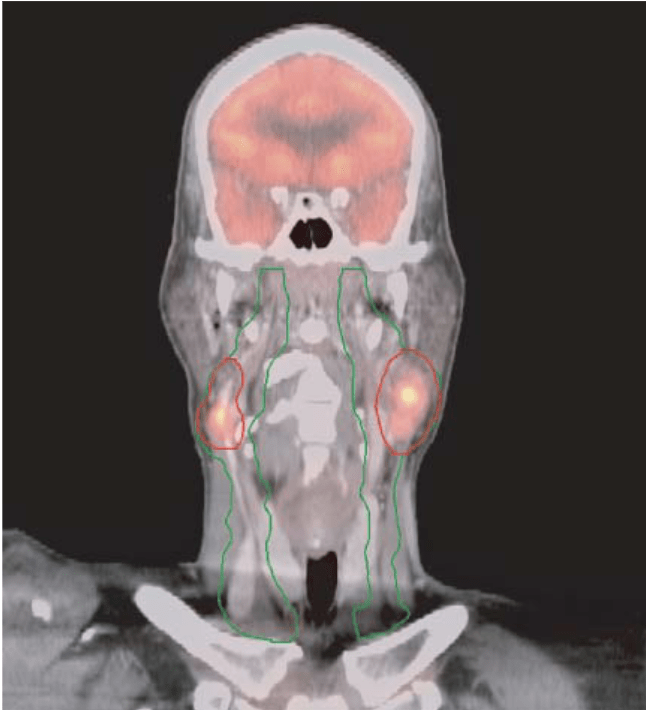

Radiation Planning: MSKCC Contouring & Dose Specifications

Target Volume Definitions

CTV Nodal:

- Gross nodes + 5 mm (no additional margin if >3cm)

- Entire involved nodal level

- No intentional ECE coverage required

CTV Elective:

- Bilateral levels II-IV (standard)

- Level IB if oral cavity involvement

- Retropharyngeal if posterior pharyngeal wall

- Well-lateralized T1-2 tonsil + single node → ipsilateral only

PERSISTENT HYPOXIA (16%):

- PTV_7000: Hypoxic gross nodes only

- Additional 2 Gy Ă— 20 fractions = 40 Gy boost

- Total 70 Gy to hypoxic nodes

- 7 weeks total treatment time

Critical Innovation:Â Universal elective dose of 30 Gy (vs historical 50-63 Gy) dramatically reduces toxicity while maintaining excellent regional control. This represents a paradigm shift in elective nodal treatment.